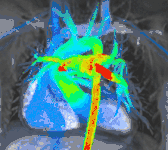

جریان چهار بعدی CMR

تصویربرداری کنتراست فاز معمولی را میتوان با استفاده از شیب حساس به جریان در ۳ طرح متعامد در یک حجم سه بعدی در طول چرخه قلب افزایش داد. چنین تصویربرداری چهاربعدی، سرعت جریان خون در هر وکسل را در کد رمزگذاری میکند و باعث میشود دینامیک سیال با استفاده از نرمافزارهای ویژه قابل مشاهده باشد. برنامههای کاربردی در بیماری پیچیده مادرزادی قلب و برای تحقیق در مورد ویژگیهای جریان قلب و عروق وجود دارد - اما به دلیل پیچیدگی مراحل پس از پردازش و زمان کسب نسبتاً طولانی در استفاده روتین بالینی نیست.[23]

جریان داخل و خارج از قلب در یک حجم چهار بعدی با زمان حل شده شامل قلب و عروق بزرگ مشاهده میشود.

سمت چپ: سرعت جریان. مرکز: خطوط جریان. سمت راست: بردارهای جریان.کودکان و نقض مادرزادی قلب